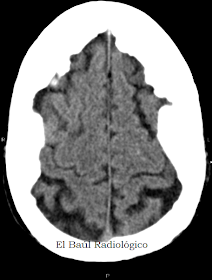

B) HIPEROSTOSIS ENDOCRANEAL DIFUSA: En la hiperostosis craneal difusa el proceso se extiende más allá del hueso frontal hasta los parietales (Figura 7). Puede simular un proceso patológico. Es más raro.

FIGURA 8) En esta imagen axial de TC craneoencefalica, correspondiente a la misma persona, se aprecia el parenquima encefálico protegido por los huesos engrosados del craneo.

FIGURA 9) Con ventana de hueso se puede apreciar el engrosamiento del díploe y el contorno mamelonado de la tabla interna del craneo, hallazgos característicos de Hiperostosis Craneal Difusa Idiopática.

FIGURA 13) Mamelones óseos de hiperostosis craneal interna en un corte más cefálico.